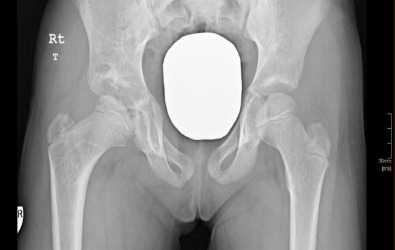

Η εικόνα απεικονίζει την διενέργεια αρθρογραφίας από περιστατικό του Δρ. Ζένιου.  Η εξέταση αυτή βοηθάει αρκετά στον προ-εγχειρητικό σχεδιασμό πριν από την ανάταξη  ισχίου.

Προ-εγχειρητικά

Μετ-εγχειρητικά